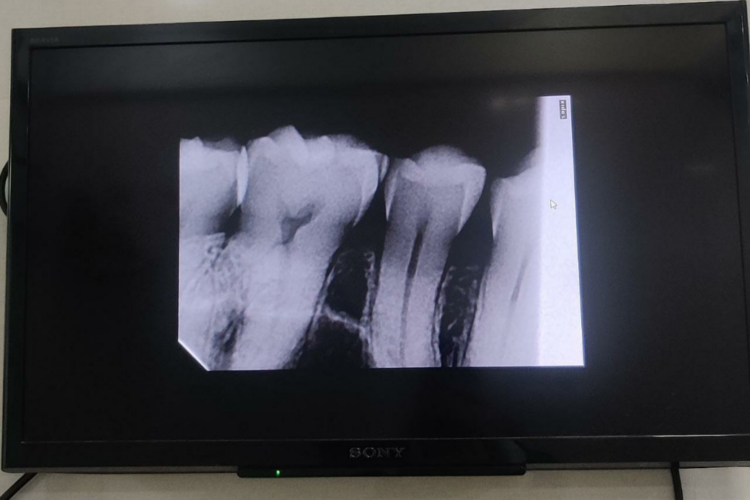

Digital X-Rays

Digital X-Rays have several benefits. They use 70% less radiation than traditional film X-Rays.

They’re quicker, have better viewing quality, and are easily transferable to other dentists, if required. They are also less expensive and more environmentally-friendly.

They also use streamlined designs, thereby taking the pain out of taking dental X-Rays.

Digital Display For Consultation

We use digital display to provide you with consultation for viewing non-diagnostic medical imagery and education about the treatment.